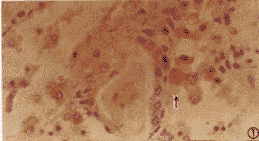

HCV NS3、NS5和CP10抗原阳性颗粒呈棕黄色、密集,定于肝外组织细胞浆内,呈均质型,包函体型和膜下型,未见核型。肾脏的肾小管上皮细胞、间质细胞(图1)和肾小球细胞内存在HCV抗原,以前两种细胞内常见,后者偶可见到。肾皮质内表达阳性细胞数量较髓质多。胰腺的腺泡细胞和腺导管上皮细胞(图2),肠道的肠腺上皮细胞(图3)和心脏的心肌细胞(图4)内也可检出HCV抗原。

图1 HCV NS3阳性表达位于肾间质细胞浆内,呈棕黄色(↑指),均质型;点状分布;S-P法(DAB染色—下同)×400

肝外脏器内抗原表达阳性细胞数量较相应肝组织(阳性肝细胞数量<1%)有较明显偏少;不同脏器间亦有一定差异,如心脏内较肠道、肾脏和胰腺偏少等。阳性细胞常以单个或数个聚集呈小灶状散在于组织内,多见于心脏和肾脏;也可数个以上聚集成不规则小片状,多见于胰腺和肠道。抗原表达阳性细胞的形态和大小与表达阴性细胞类似,未见特殊病变。